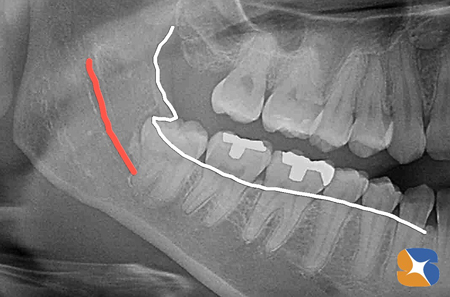

名古屋から石切に到着されたのが、PM4:00。まずCT撮影をして親知らずの歯の周囲骨の情報収集を始めました。その間、予約の患者様の治療をひたすら進め、抜歯に必要な時間を作る準備を始めました。CT撮影の結果、名古屋の先生方のおっしゃる通り、太い神経は歯の根の先を走り、骨は

歯をがっちり囲んでいるため、『これは一筋縄ではいかない抜歯』が予測されました。『急患でこの抜歯は確かにきついな…』さらに、『明日から出勤なので、痛みは薬でなんとかするので、顔だけは腫れないようにして欲しい』というリクエストに応えれるかどうか考えましたが、状況が状況なだけに抜歯を決断しました。